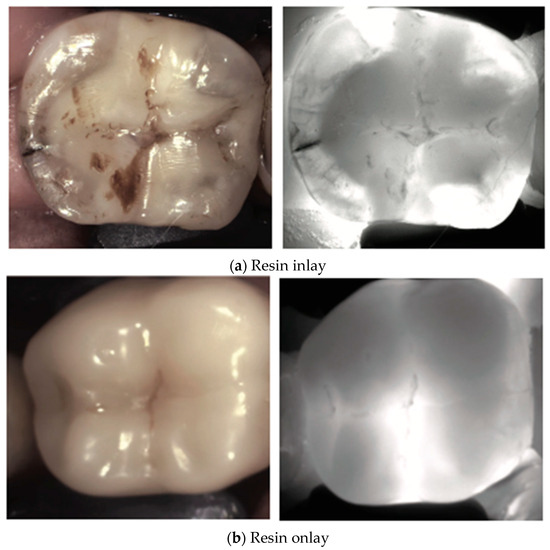

3. Restored Teeth